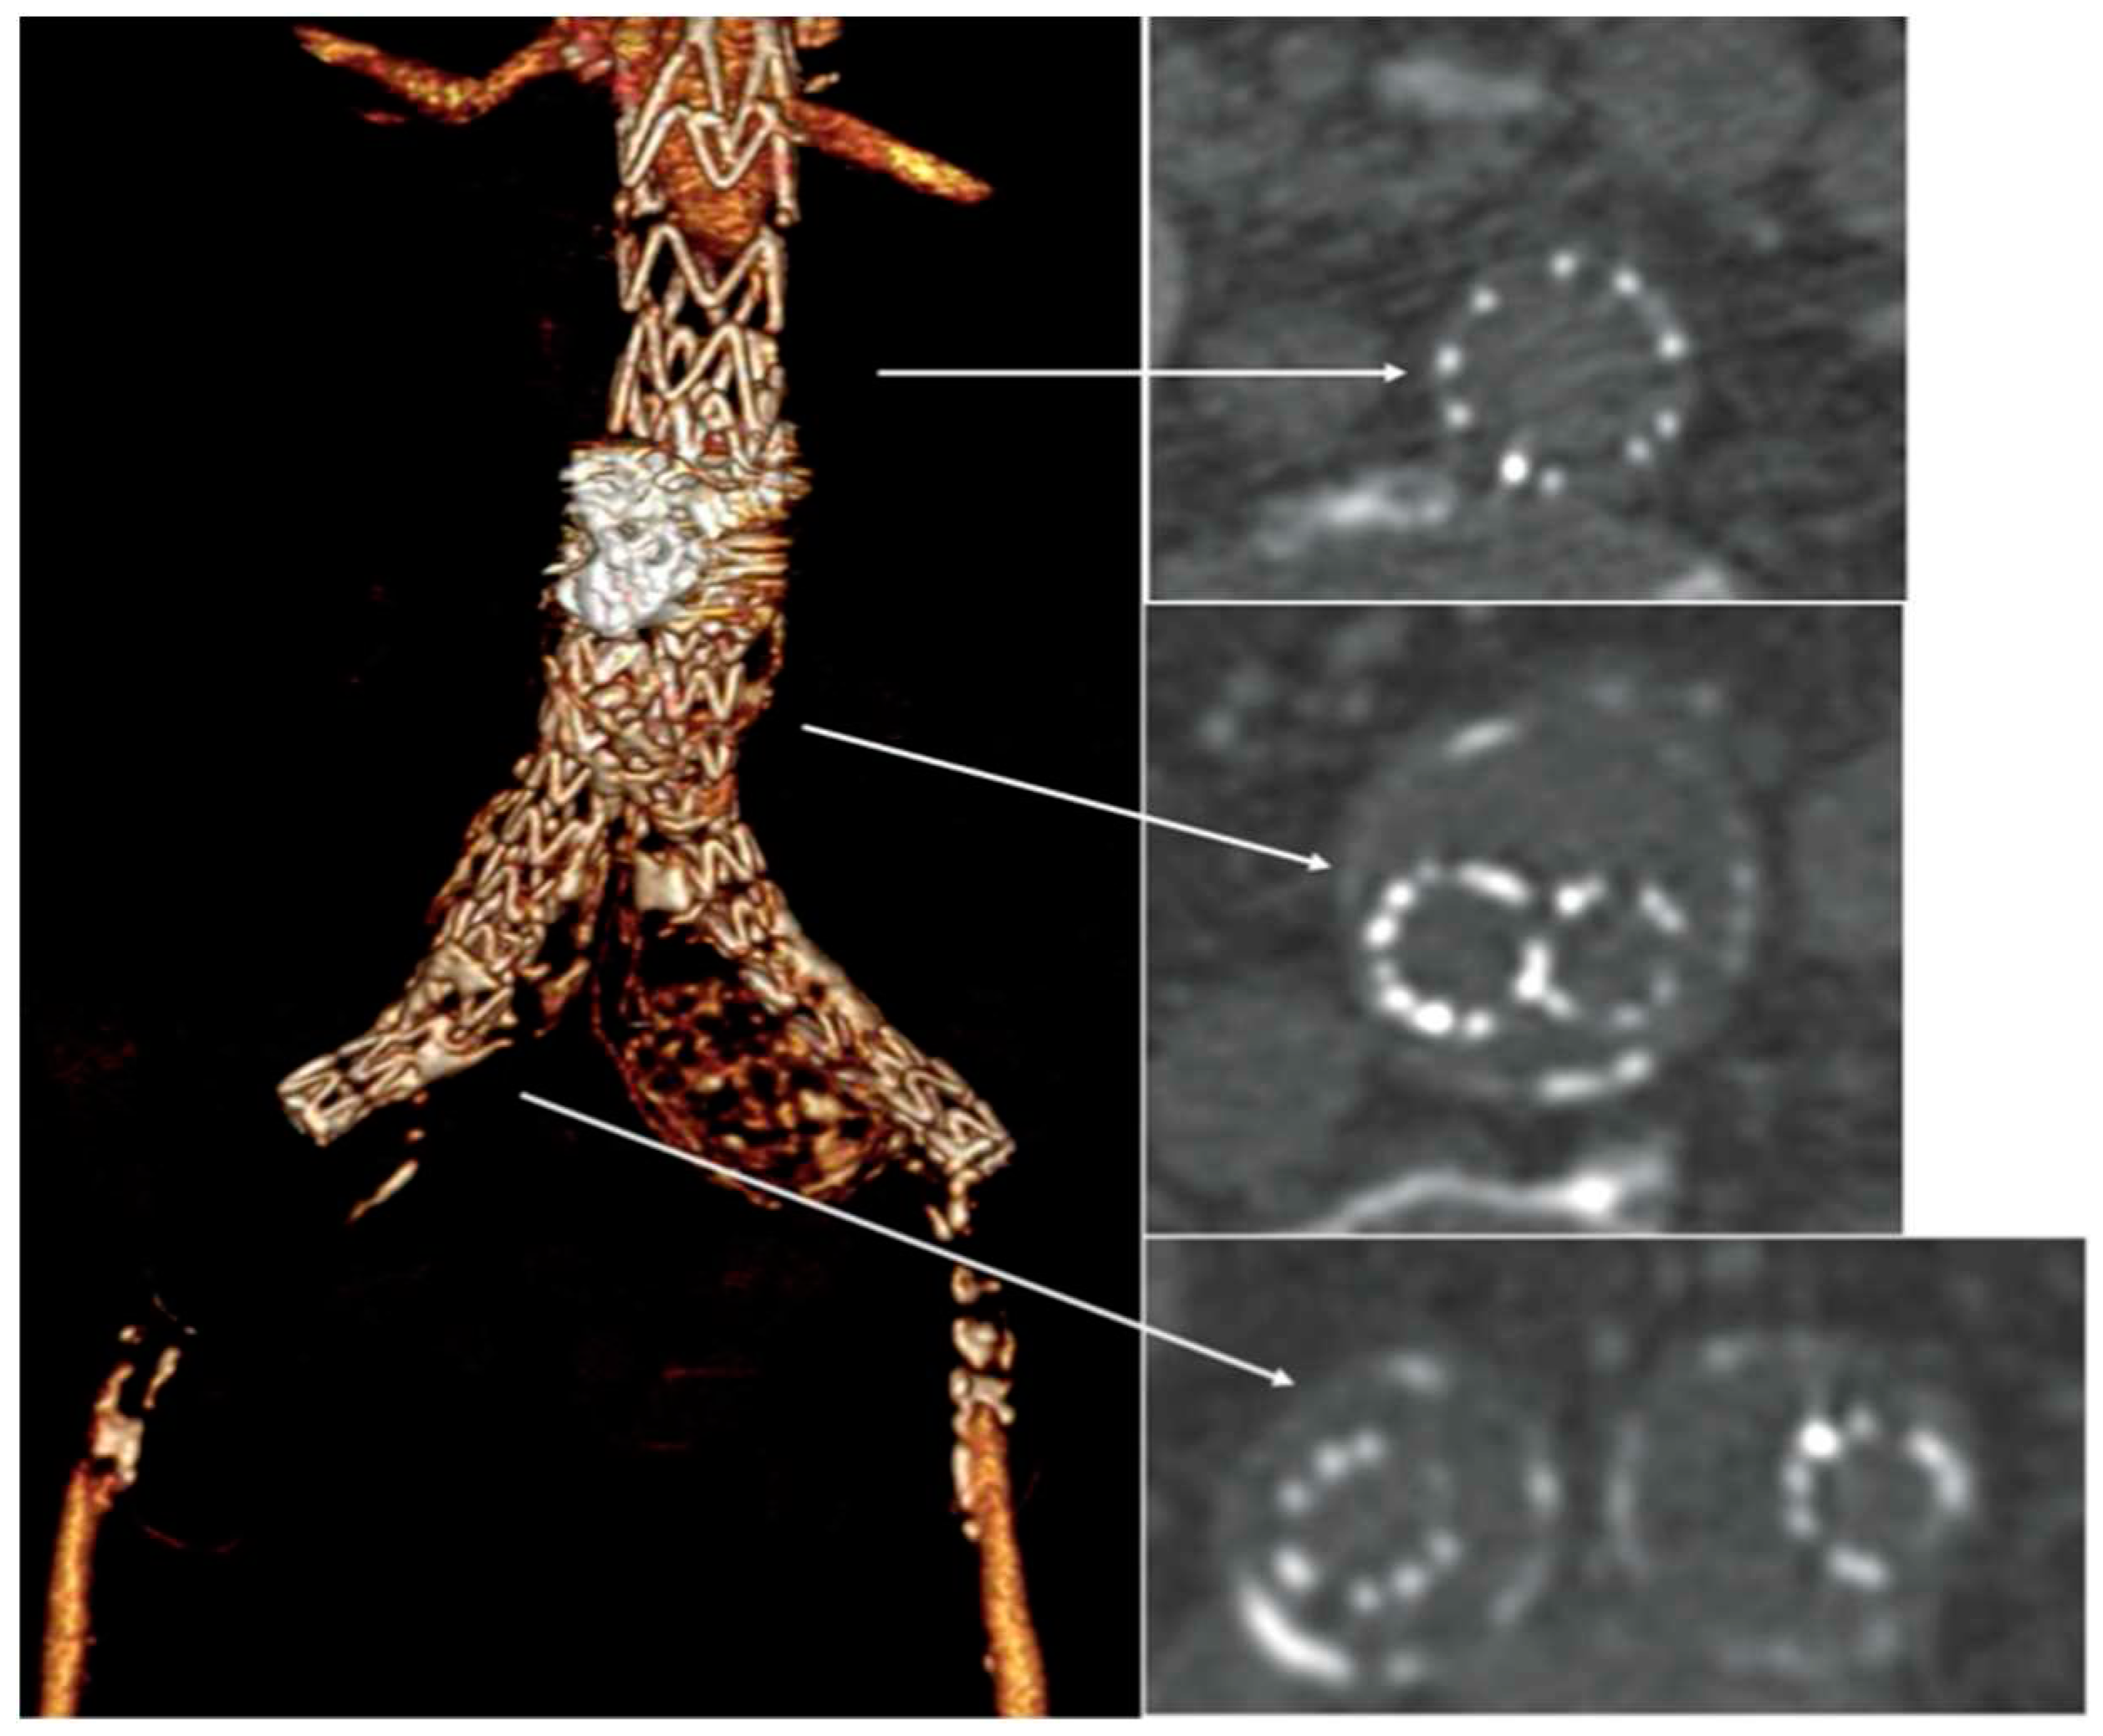

A bedside DUS examination showed the patency of the suprarenal aorta, and the complete thrombosis of the aortic stent-graft without detectable blood flow at the femoral level. An urgent CTA confirmed the complete endograft’s thrombosis with common femoral arteries’reconstitution through collateral circulations (Figure 2), and the thrombosis of the right popliteal artery aneurysm.

Figure 2. Emergency computered tomography showed the complete endograft’s thrombosis with common femoral arteries’reconstitution through collateral circulations.